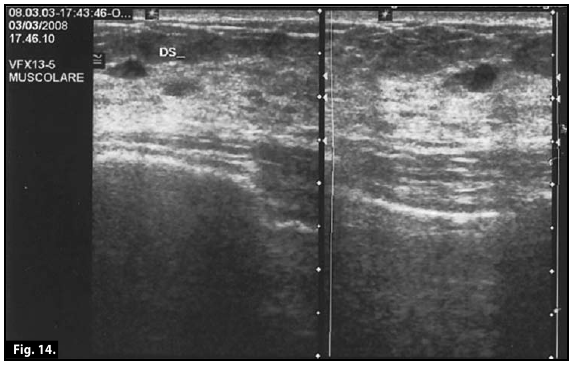

Ultrasound scan...